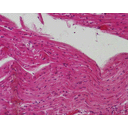

SISTEMA MUSCOLARE

180px-Skeletal_muscle_-_cross_section,_nerve_bundle[1].jpg